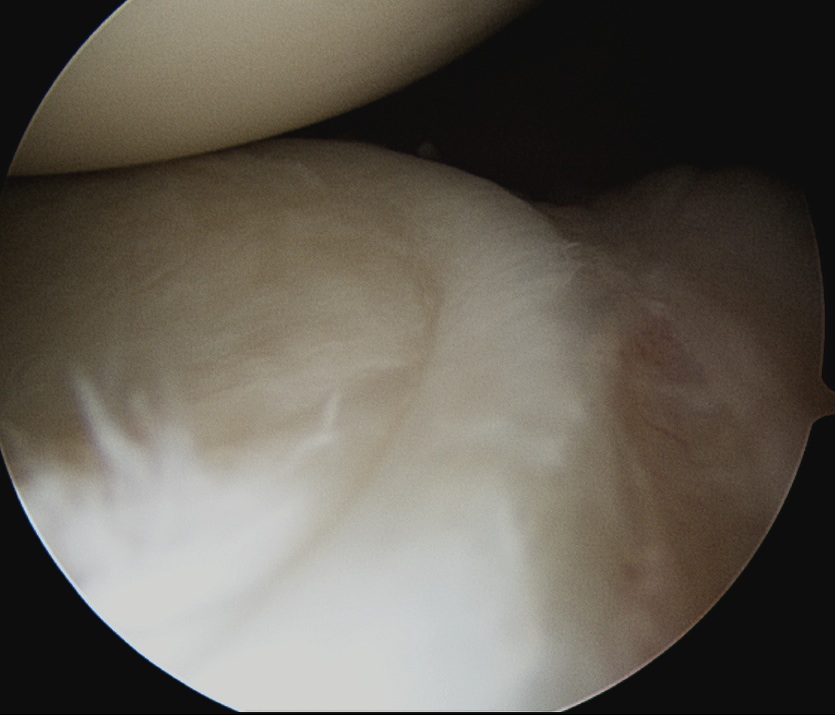

Undersurface supraspinatus - abduct arm

Infraspinatus / bare area / Hill Sachs

Subacromial space